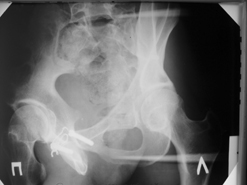

Диагноз : Сочетанная травма. ЗЧМТ. Перелом свода черепа. Ушиб головного мозга.Разрыв лонного и крестцово-подвздошного сочленений с нарушением целостности тазового кольца, с массивной забрюшинной гематомой и пропотеванием в брюшную полость. Перелом 10 ребра справа, осложненный гемопневмотораксом справа, правосторонней пневмонией на фоне ушиба правого легкого. Шок 3-4 ст. Больной поступил в отделение 07.03.2005г. в 16.00 в экстренном порядке через 30 минут после автодорожной травмы.Доставлен КСП. При поступлении состояние больного крайне тяжелое, явления травматического шока, А/Д-80/60 мм.рт. ст. ЧСС-120.В экстренном порядке поднят в операционную, интубирован, совместно с диагностическими мероприятиями лечение шока.При осмотре выявлены перелом 10 ребра справа, разрыв лонного и правого крестцово-подвздошного сочленений. Имеется линейный перелом теменной и височной костей слева с переходом на основание. Диагностическая лапароскопия 07.03.2005г. в 16.30-массивная забрюшинная гематома малого таза.Оставлена контрольная, дренажная трубка.Учитывая кровь в моче произведена цистография - данных за разрыв мочевого пузыря не найдено. Больной переведен в реанимационное отделение.За 08.03.2005г. из брюшной полости выделилось до 1500,0 мл, крови, часть крови реинфузирована. 08.03. в 06.30 наложен торокоцентез справа,удалено 100,0 мл. крови и 200,0 мл. воздуха .. Учитывая продолжающеееся кровотечение в брюшную полость из перелома костей таза, для исключения возможного разрыва внутренних органов 09.03.2005г. произведена Видеолапароскопия., на которой повреждения органов брюшной полости не выявлено.Одновременно произведен шов лонного сочленения проволокой и винтами, с одномоментным наложением стержневого аппарата на кости таза, с целью уменьшения кровотечения из разрывов тазовых сочленений, дренирование гематом. В последующем состояние больного оставалось тяжелым. 10.03.наложена нижняя трахеостома.Далее неоднократно производилась лечебно-диагностическая ФБС.С 10.03 выявлена правосторонняя плевропневмония. КТ головного мозга от 10.03-субарахноидальноекровоизлияние.Срединные структуры не смещены. КТ-контроль от 15.03-открытая моновентрикулярная гидроцефалия4 желудочка. Полисинусит. Постепенно состояние больного медленно прогрессировало к улучшению.С 24.03 переведен на самостоятельное дыхание, а 09.03 переведен в травматологическое отделение.Аппарат стержневой снят из-за перелома стержня (раскрутил больной самостоятельно).После госпитализации в наше отделение проведено дополнительное обследование Рентгекнография, КТ.Хотелось бы услышать Ваше мнение о дальнейшей тактике.-- С уважением, Leonid

Углядел билатеральное повреждение таза. Имеется вертикальная нестабильность со стороны перелома боковой массы крестца, ротационная с контрлатеральной стороны - чрезподвздошный разрыв кп сочленения. Разрыв лона, запирательные отверстия вроде целы.

DS. на сегодняшний день: Вертикальная двусторонняя нестабильная деформация таза, неправильно срастающийся перелом боковой массы крестца слева, срастающийся перелом крыла правой подвздошной кости, застарелый частичный разрыв правого кп сочленения, застарелый разрыв лонного сочленения.